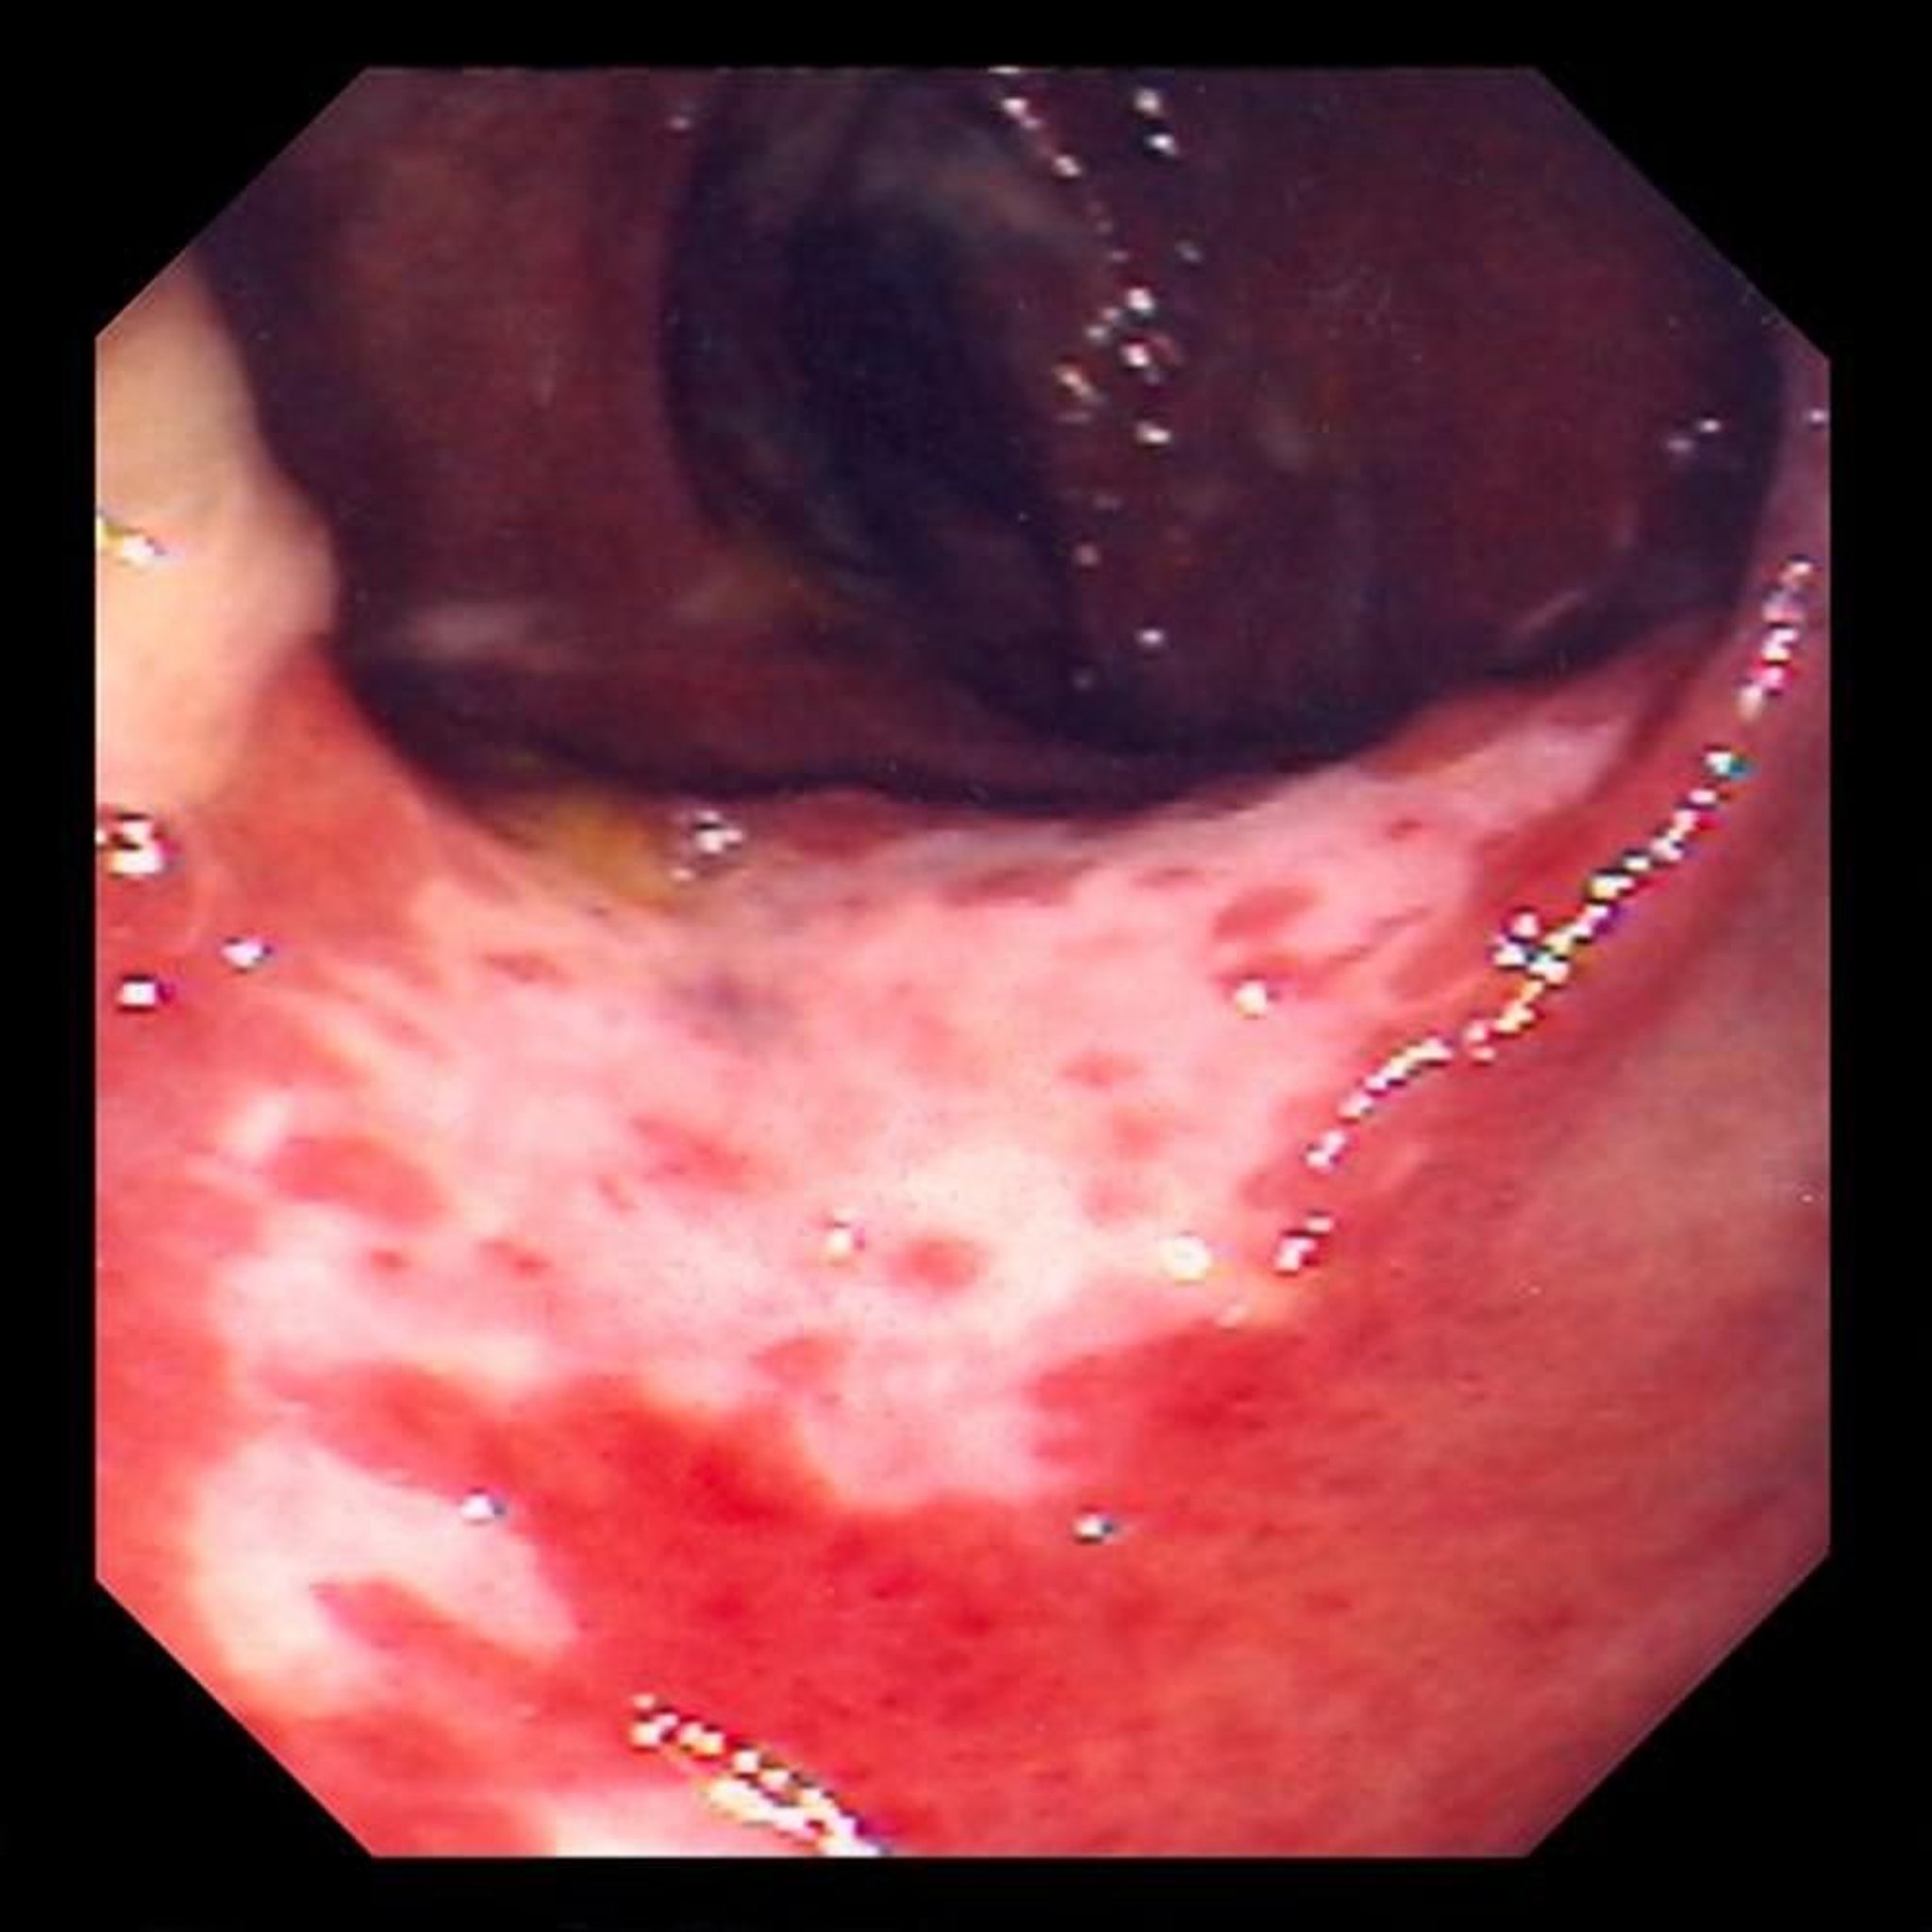

Ischämische Kolitis (Koloskopie)

Dieses Foto zeigt eine durch eine Durchblutungsstörung verursachte Schädigung der Darmschleimhaut. Die Darmschleimhaut ist rot und mit Geschwüren bedeckt (weiße Bereiche).

Foto von David M. Martin, MD.